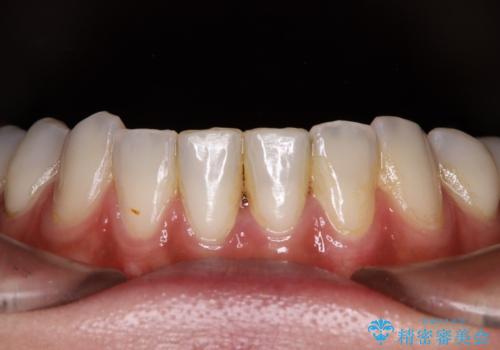

インプラント部は治癒待ちの期間が長くなるため、その期間を利用して下顎の叢生を解消し、より理想的な咬み合わせで補綴治療を行うこととしました。

途中通院されなかった時期が何度かあったため、初診から4年以上の年月がかかりましたが、比較的スムーズに治療を進めることができました。

下顎前歯の歯列を整えたことで、上顎前歯の咬み合わせが安定し、自然な口元に仕上げることができました。